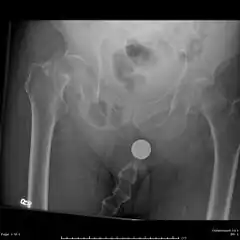

Radiography

.jpg)

Anterior-posterior (AP) and lateral radiographs are typically obtained.[4]

In order to rule out other injuries, hip, pelvis, and knee radiographs are also obtained.[5]

The hip radiograph is of particular importance, because femoral neck fractures can lead to osteonecrosis of the femoral head.[4]